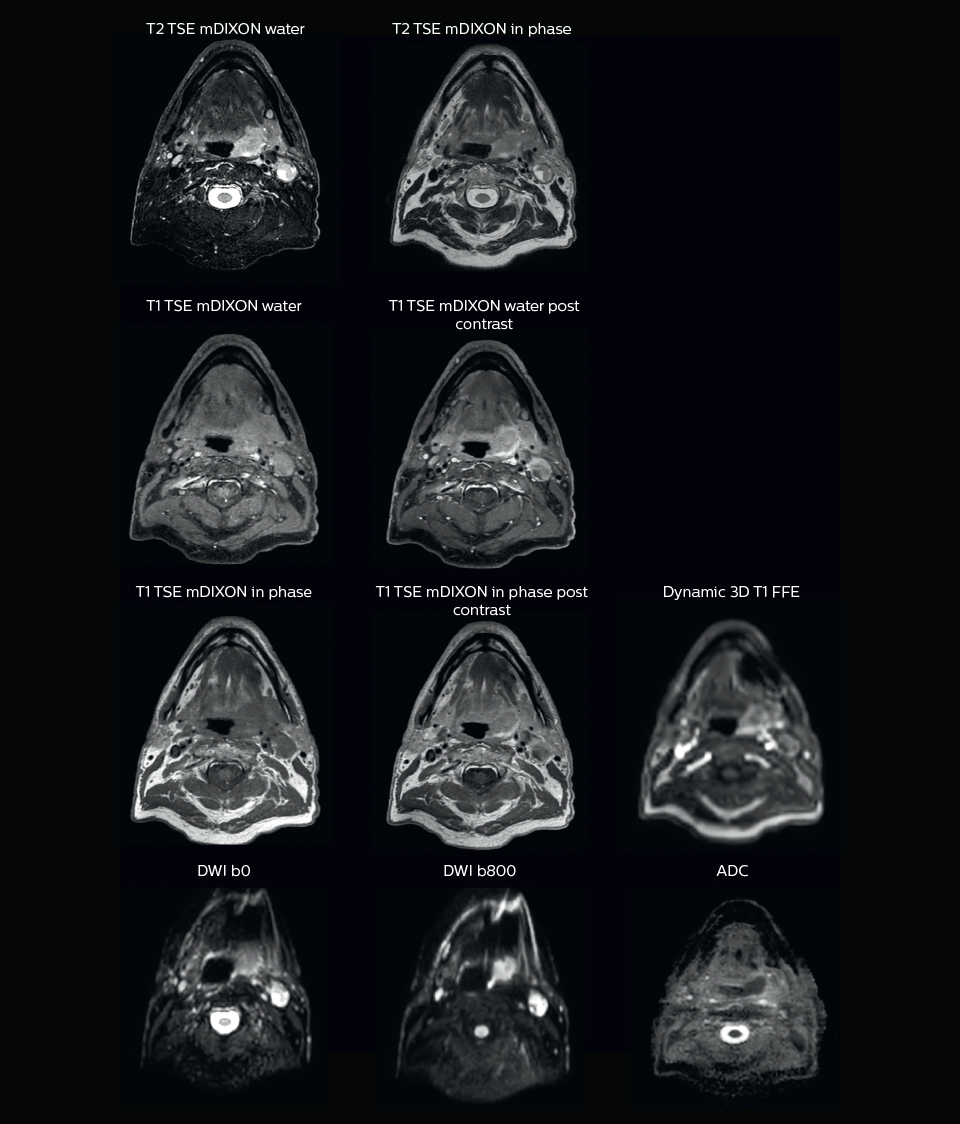

“In patients with a primary tumor in the head and neck area, we do use MRI in daily clinical radiation therapy practice to visualize the tumor and critical structures. This may be used to help sparing of critical structures, such as the parotid glands, submandibular glands, esophagus, optic nerves, brain stem and spinal cord [7]. And postoperatively we scan patients that have tumor growth along the cranial nerves for target delineation,” says Dr. Philippens.

“Because of the challenges posed by CT-MRI coregistration in this area with many degrees of freedom for motion, we image these patients in a radiotherapy mask. However, one disadvantage of using the mask is that a regular head and neck coil cannot be used; a dedicated coil solution would be needed for imaging with a mask.

For this we make use of flexible coils that we position close to the target area. This setup can also be combined with the anterior coil for a larger coverage and enhanced SNR.”

“We use pre- and post-contrast T1- and T2-weighted sequences with the fast and robust mDIXON method for fat suppression,” says Dr. Philippens. “Dynamic contrast-enhanced imaging is performed with high temporal resolution and low spatial resolution, to see the contrast agent uptake in the tumor. Diffusion weighted imaging is used qualitatively to see how the tumor extends into another structure, rather than for strict delineation.”

“In postoperative patients who have had tumor growth along the cranial nerves, we use T2-weighted gradient echo (FFE) on our 3.0T MR-RT scanner to show the nerves for target delineation and look to see if there is still tumor left.”